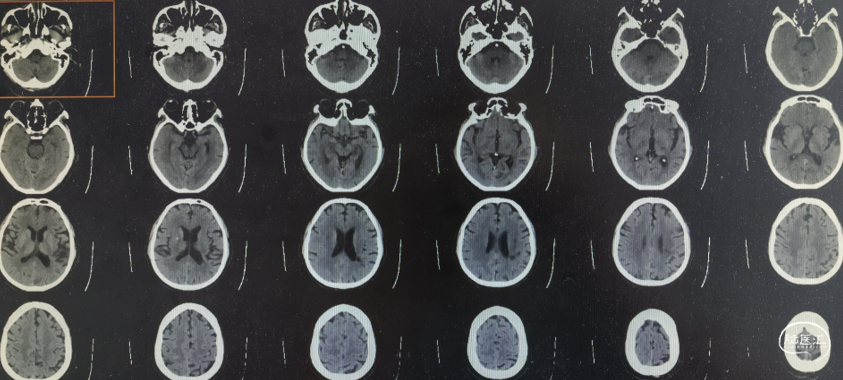

➢术后头颅CT

第二次住院,夜间再发头晕、呕吐、视物重影,约10分钟后好转。次日早晨来院,入院查体未见阳性体征,行急诊头颅MRI+DWI:未见急性梗死病灶。

头颅MRI:未见新鲜脑梗死

DWI: